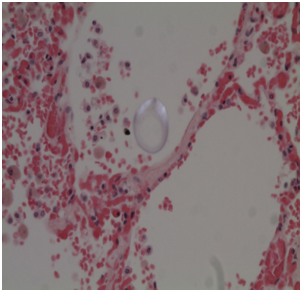

Histology: Acute emphysema was the prominent observation; edema and hemorrhages were also present.4 In 9 cases (Figures 3-6), exogenous material in the airways, comprehensive of planktonic boli in the lower branches, clearly demonstrable at polarization microscope (and possibly confirmable at SEM’s elemental analysis with EXD). Zoo- and phytoplankton have been better identified in the UV microscope. It is mandatory to differentiate the planktonic material from gastric content, regurgitated and aspirated (Figure 7 & 8).

Figures 3,4 Drowning in seawater. Images of endoalveolar zooplankton (protoconch of crustacean) (EE, 480 X, polarized light).